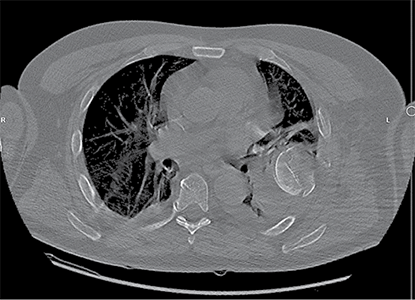

A 58-year-old patient was admitted to the Emergency Department of level I Trauma Center in August 2022 due to polytrauma sustained in a car accident. On arrival, the patient’s condition was severe, with decreased consciousness (GCS score of 12), unstable hemodynamic, subcompensated peripheral circulation, blood pressure of 62/32, and heart rate of 78 beats per minute. There was reduced breathing on the left side with a respiratory rate of 18 breaths per minute and an oxygen saturation (SpO2) of 85.0%. Palpation revealed pain in the left posterior chest. X-rays and CT scans were performed, which revealed a traumatic hemothorax on the left side, humeral head within the pleural cavity, three rib fractures, lung contusion, and hematoma.

Figure 2. Subsequent 3D reconstruction